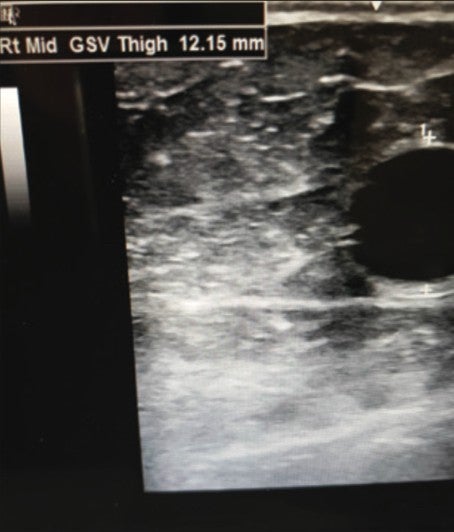

- Mid-GSV thigh: 2.6 seconds (Figure 2)

Figure 2. Pre-Varithena Treatment Rt. Mid-GSV Thigh: 2.6 seconds